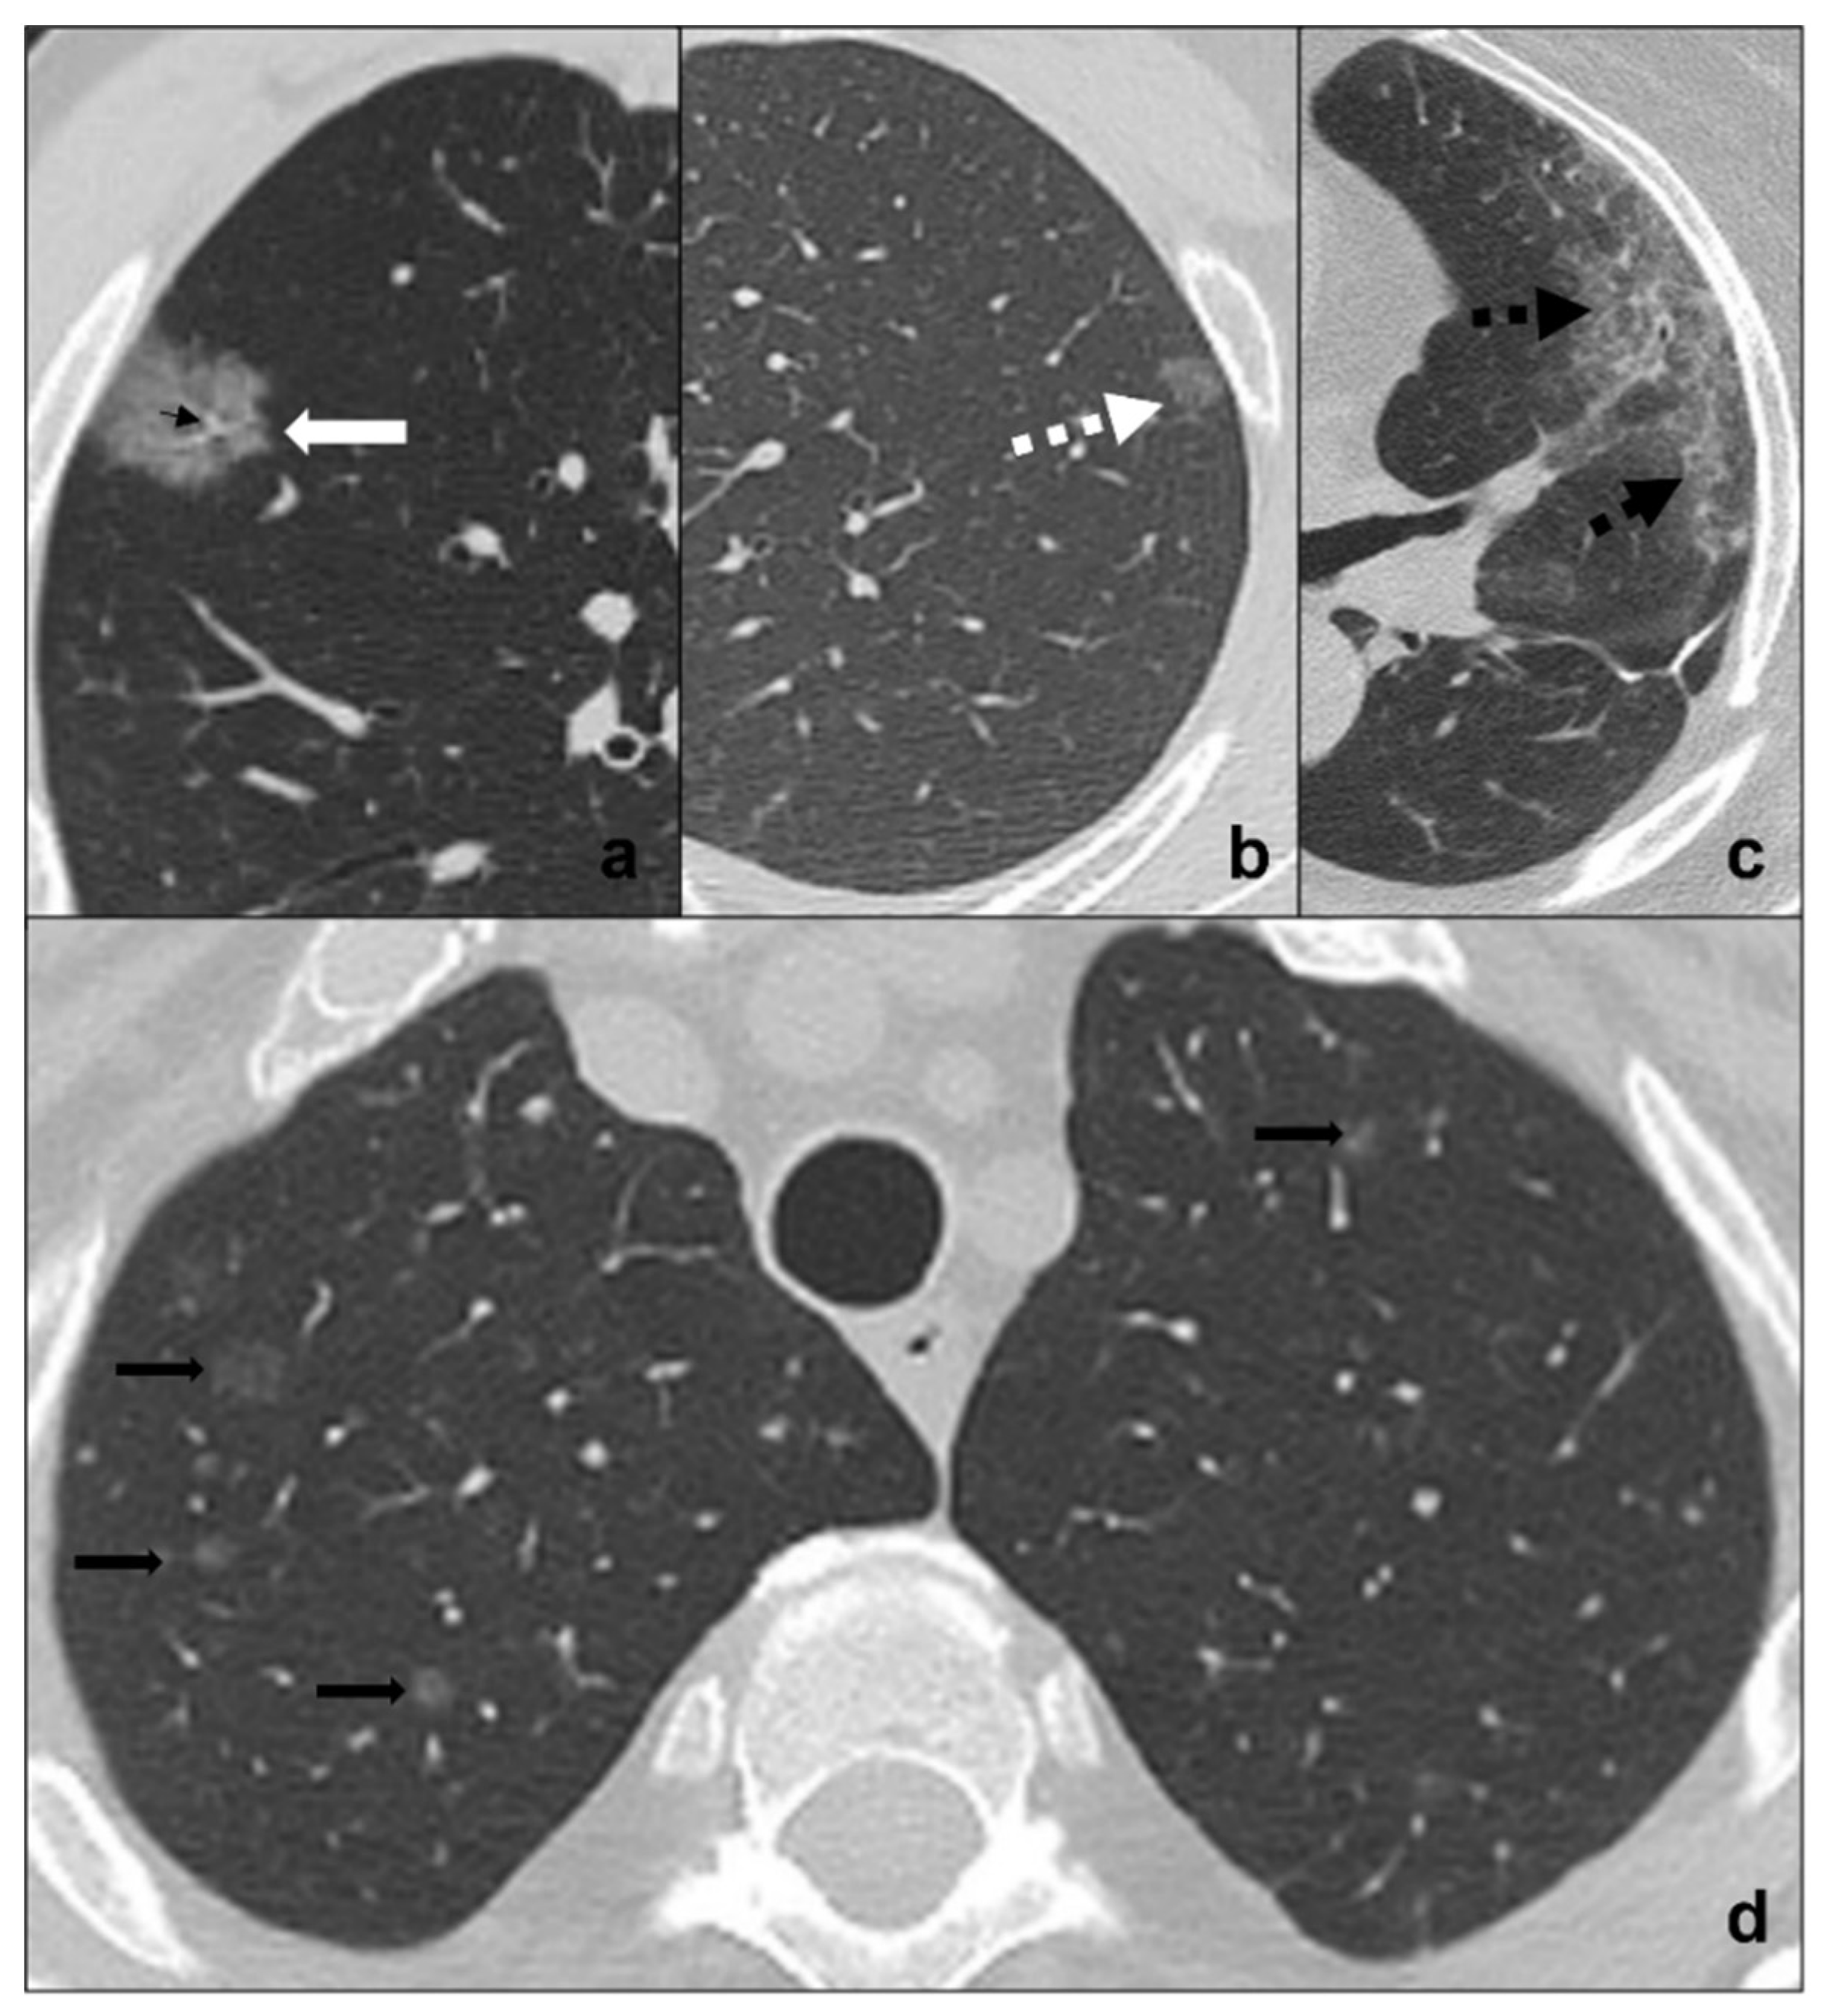

Figure 2.

(a–d) HRTCs showing differential diagnoses of COVID-19 pneumonia stage 1/ground-glass opacities. COVID-19 phase 1 is characterized by subpleural ground-glass areas (white arrow in (a)) with ectasis vessels within (black arrow in (a)). Its main differentials are represented by adenocarcinoma in situ, presenting as a focal area of ground-glass opacity (dotted black arrow in (b)); radiation pneumonitis (acute radiation-induced lung disease) presenting with ground-glass opacities (dotted black arrows in (c)) in the field of radiation; and ground-glass metastases (black arrows in (d)) which appear as multiple focal ground-glass opacities with a random distribution. Lungs: mean window with 1500 HU; mean window level −600. Mediastinum: mean window with 350 HU; mean window level 50 HU.

Radiological features for differential diagnosis between precursor glandular lesions and COVID-19 pneumonia (Figure 2a,b) [34,35,36]):

- generally single and focal ground-glass opacity;

- distribution is random and may be centro-parenchymal or subpleural;

- asymptomatic and resistant to antibiotic and anti-inflammatory treatment;

- tendency to grow and/or evolve to malignancy with different timing with respect to COVID-19 pneumonia.

Ground-glass metastases are less frequent than solid metastases and present as multiple focal areas of ground-glass opacities with a random distribution. Although patients commonly present with an already-known primitive tumor diagnosis and do not present acute symptoms, ground-glass metastases may be the presentation of cancer [37,38,39] (Figure 2d).

Radiological features for differential diagnosis between ground-glass metastases and COVID-19 pneumonia [37] (Figure 2a,d):

- evidence of coexisting solid/subsolid lung cancer or systemic known cancer;

- bilateral involvement with a random distribution in case of hematogenous spread or with spread thought airspace (STAS);

- ground-glass opacities do not follow COVID-19 phases and are generally asymptomatic in early phases;

- growing despite antibiotics and anti-inflammatory therapies;

- pleural effusions;

- mediastinal lymphadenomegalies.

Figure 3.

(a–c) HRTCs showing differential diagnoses of COVID-19 pneumonia stage 2/crazy-paving opacities. In stage 2, extensive, subpleural crazy-paving opacities (black arrows in (a)) coexist with subpleural areas of ground-glass (white arrow in (a)) and should be differentiated by lymphangitis carcinomatosis (b), which represents secondary spread of lung cancer to the lymphatic vessels and is frequently seen together with pleural effusion (black asterisk in (b)), and by radiation pneumonitis (acute radiation-induced lung disease) presenting with crazy-paving pattern (dotted black arrows in (c)) in the field of radiation. Lungs: mean window with 1500 HU; mean window level −600. Mediastinum: mean window with 350 HU; mean window level 50 HU.

Radiological features for differential diagnosis between lymphangitis carcinomatosis and COVID-19 pneumonia [40,42] (Figure 3a,b):

- evidence of coexisting solid/subsolid cancer;

- unilateral involvement, which is homolateral to lung cancer;

- crazy paving pattern is typical, but does not coexist, follow, or precede

- ground-glass opacities and consolidations, that are typical, respectively, of stage one and three of COVID-19 pneumonia;